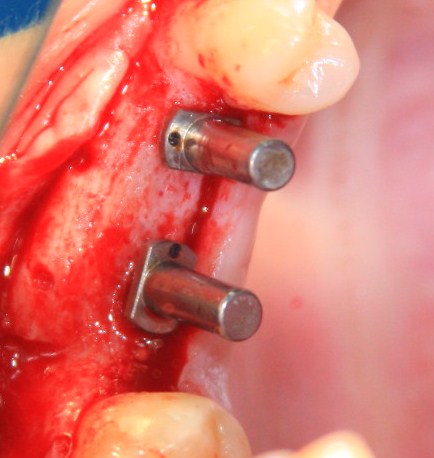

Простой. Надежный. Дешевый. Способ остеопластики.